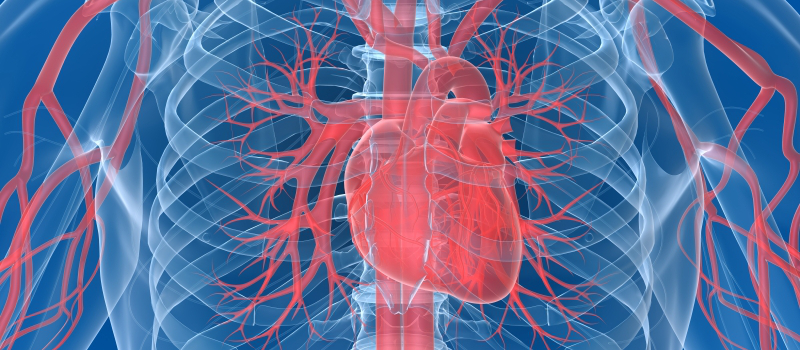

Hjertet har form som en kjegle med spissen (apeks) ned og den brede delen, bunnen (basis) opp. Hjertet er pakket inn i hjerteposen, som kalles perikard. Perikardet består av to lag.

Hjertet har 4 hjertekamre

Hjertet består av fire hjertekamre. Forkamrene (atriene) og hjertekamrene (ventriklene)

- Høyre forkammer

- Venstre forkammer

- Høyre hjertekammer

- Venstre hjertekammer

Blodet flommer alltid kun èn vei gjennom hjertet

Før vi går videre er det viktig å huske på at blodet alltid flommer i samme retning gjennom hjertet. Rekkefølgen er slik:

- Fra den store venen Venae Cava og inn i høyre atrie

- Fra høyre atrie til høyre ventrikkel

- Fra høyre ventrikkel, via lungene til venstre atrie

- Fra venstre atrie til venstre ventrikkel

- Fra venstre ventrikkel til hovedpulsåren, aorta.